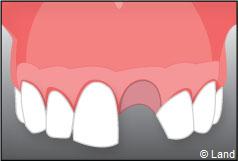

Exemple d’un implant unitaire pour remplacer une dent antérieure manquante.

– le remplacement d’une dent unitaire. Grâce à ce procédé, il n’y a pas de mutilation des dents voisines.